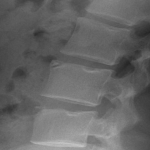

2. Limbus Bone

A limbus bone is an unfused secondary ossification center of the vertebral body (typically the anterosuperior corner), due to herniation of the nucleus pulposus through the ring apophysis prior to skeletal development. This fragment remains ununited to the vertebral body throughout the patient’s life. This can be differentiated from a fracture in that it is well-corticated, triangular, and the fragment of bone will not exactly “fit” into the defect. These fragments may be smaller than the defect of the bone (figure 2) or they may hypertrophy over time and become larger (figure 3). A limbus bone is most often asymptomatic.